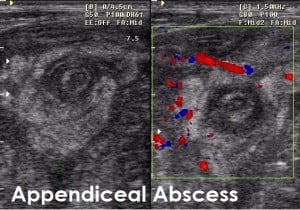

- Abdominal ultrasound in males with complex signs (e.g. Palpable mass in RIF)